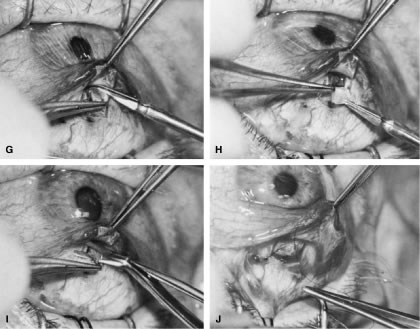

After the iridectomy is complete, the iris usually will return spontaneously into the anterior chamber unless it has suffered damage as a result of high pressure (as occurs in severe attacks of angle closure glaucoma). In patients with a reactive sphincter, it usually is necessary only to release the iris from the grasp of the incision. The iris can be stroked into position with the use of a blunt instrument on the corneal surface. Attempting to reposit the iris by directing a stream of irrigating solution into the incision is not recommended; the solution may enter the posterior chamber, forcing even more iris out of the incision. If the surgeon has difficulty restoring the iris to its proper position, injection through the previously placed paracentesis track of freshly mixed acetylcholine usually will solve the problem. In the eye with a dilated fixed pupil and a flaccid iris, it often is preferable to perform a sector iridectomy. Once the pupil is entirely round, the suture placed previously in the corneoscleral incision can be pulled up and secured promptly. Injecting balanced salt or acetylcholine solution through the previously placed paracentesis can deepen the chamber. In patients who have had recent angle-closure attacks and in whom peripheral anterior synechiae may be newly developed, forceful deepening of the anterior chamber at this point may tear open the synechiae and restore normal function of the anterior chamber. The procedure of chamber deepening must be done cautiously, with careful monitoring of IOP. A gonioprism, such as the Zeiss four-mirror lens, can be used with an operating microscope to monitor the effect on anterior chamber angle. At the close of the procedure, the pupil should be round, the chamber deep, and the incision sufficiently closed that there is no leakage. The IOP should be approximately 15 to 30 mm Hg, being raised to that level by injection through the keratostomy. Such a pressure may help prevent subsequent choroidal detachment and allows the integrity of the incision to be tested. If the corneoscleral incision has been properly placed and sutured, there should be minimal transient astigmatism. Vision should return to the preoperative level within several days. If the eye is inflamed, it usually is helpful to instill a short-acting cycloplegic agent such as cyclopentolate. Furthermore, the surgeon may give a subconjunctival injection of corticosteroid, although it rarely is necessary to do so. An antibiotic ointment and a light patch usually are applied until the facial nerve block has worn off. If there is a reasonable chance that the patient will need a filtration procedure at a later date, then the surgical procedure is modified to perform the iridectomy through clear cornea, rather than under a fornix-based flap. The technique is almost exactly the same, with the obvious exception that the incision is placed through clear cornea. Postoperative Care In almost all instances, iridectomy can be performed as an outpatient procedure. However, when associated with severe pain or when the attack of angle closure has been difficult to stop and has required extensive usage of carbonic anhydrase inhibitors and osmotic agents, admission of the patient to the hospital may be justified. Especially in older and infirm patients, the general state of health must be monitored carefully. It is important to verify that the patient has not become overly dehydrated or experienced an attack of congestive failure. The eye patch usually is removed from the treated eye as soon as the facial nerve block has worn off. If the procedure is done on an outpatient basis, a patch and shield may be left in place until the patient returns the next day for the first postoperative visit. A drop containing a corticosteroid can be used topically three or four times a day until the inflammatory response has disappeared, usually 4 to 7 days. Careful attention must be paid to the state of the pupil. The development of posterior synechiae is an important and usually unnecessary complication. Although it is not clear that posterior synechiae predispose the patient to the development of cataract, the presence of such adhesions makes extracapsular cataract extraction more difficult. Because many patients with angle-closure glaucoma will later have cataract extraction, the development of such adhesions may jeopardize the long-term visual result. Furthermore, inability of the pupil to dilate in the dark may limit the patient's visual function, especially in conjunction with a developing cataract. In most cases, dilating drops are used routinely until the inflammatory response has worn off. One acceptable program is to use tropicamide 1% at sufficient intervals to ensure that the pupil is dilated adequately for a period of approximately 1 week. The medication can be continued at bedtime for 2 to 3 weeks, or even longer, until it is certain that the inflammatory response has disappeared. Many patients are given pilocarpine preoperatively. There is a tendency to continue the administration of pilocarpine postoperatively, especially when control of IOP has been difficult. This practice should be discouraged. Pilocarpine will predispose patients to posterior synechiae and should be avoided if possible. The drug of choice for pressure control usually is topical epinephrine, a β-blocker, or epinephrine plus a β-blocker. If these two agents are not adequate, a carbonic anhydrase inhibitor can be used until the eye is entirely quiet, at which time pilocarpine can be reinstituted. In such cases, however, care should be taken to dilate the pupil periodically to prevent the development of posterior synechiae. Some surgeons may be reluctant to use dilating drops for fear of inducing angle closure. This possibility exists, but it is uncommon. Furthermore, it is preferable to know immediately whether the iridectomy has eliminated the possibility of angle closure caused by papillary dilatation. Therefore, this concern is an additional reason to use cycloplegic agents in the immediate postoperative period. Because of the possibility of an increase in IOP after dilatation, however, IOP should be checked carefully after the use of the cycloplegic agent. In addition, IOP should be monitored carefully during the initial postoperative period. Pressure spikes are not uncommon. These spikes are of little concern if the optic nerve is healthy. However, in patients with advanced glaucomatous nerve damage, such pressure spikes can be devastating; they should be avoided if possible. Postoperative evaluations ordinarily are made on the first postoperative day, after 1 week, and after 1 month. If a problem with the control of IOP is suspected, visual fields and disc photographs should be obtained. Complications The most serious complication after iridectomy is malignant glaucoma (aqueous misdirection, ciliary block glaucoma). Eyes predisposed to this complication are those with small anterior segments, typically seen in patients with marked hyperopia or small globes. Furthermore, there is some indication that eyes with high IOP preoperatively may be predisposed as well. Patients who have had an attack of malignant glaucoma in one eye are likely to have the same complication in the second eye. GUARDED FILTRATION PROCEDURES (TRABECULECTOMY) What traditionally has been called a trabeculectomy has become the standard filtration type of surgery for most cases of open-angle glaucoma. The name is a generic one, describing a wide variety of surgical methods, some substantively different from others.46–50 A goal of the original procedure was to allow filtration out of the cut ends of Schlemm's canal. In most cases, this mechanism does not appear to be the actual reason for the decrease in IOP that usually follows. Another theoretic explanation for its pressure-lowering effect, direct access of aqueous humor to the collector channels, bypassing diseased trabecular meshwork or Schlemm's canal, may be the actual mechanism for pressure reduction in a few cases. Exploration of the operative site does not disclose any area of gross filtration in some patients who have effective pressure lowering after surgery. It is likely that in such cases, aqueous humor exits into the collector channels or perhaps through the thinned scleral tissue. In most cases, the mechanism responsible for lowering IOP after guarded filtration procedure is a through-and-through fistula connecting the anterior chamber with the subconjunctival space. As such, the word trabeculectomy is a misnomer. Complete success is possible without removing trabecular tissue. Lamellar sclerokeratectomy would be a more accurately descriptive title, and it has been suggested in the past. However, the term is cumbersome and to some extent, inaccurate, because sclera is not always removed. Because the term trabeculectomy is a significant misnomer, we rarely use it in this chapter. The procedure performed currently functions as a filtration procedure; consequently, it is appropriately called a filtration procedure. When it is performed so that the filtering area is at least partially protected in an attempt to control the amount of filtration, the term guarded filtration procedure is appropriate and is used in this chapter. Consideration of how the operation actually works is not of purely academic interest; it materially affects how the surgery is performed and influences the final result. Patients with gross fistulas with filtering blebs resembling those seen with operations that were popular in the past, such as the corneoscleral trephine, usually achieve lower IOP than patients in whom the filtering bleb is thicker, more posterior, and less cystic. Furthermore, the thinner, polycystic bleb probably lasts longer, providing more years of low IOP. Consequently, if the surgeon wants to obtain IOP that is as low as possible, the guarded filtration procedure should be designed to produce gross filtration. Such a goal has its costs, however. A general principle of glaucoma surgery is that every millimeter of pressure-lowering effect has a price. This principle applies to guarded filtration procedure; the complication rate with procedures designed to produce gross filtration and lower IOP is greater than that with procedures that are more completely guarded and in which a higher final IOP is considered satisfactory, as discussed in detail in the first section of this chapter. The surgeon must carefully consider the major goal of the surgery being planned. For example, for the patient who has uncontrollable angle-closure glaucoma and is predisposed to flat chamber or even malignant glaucoma, the surgeon probably will fashion the scleral flap and suture it in place so that leakage is minimal. On the other hand, for a patient with high myopia with glaucoma that is progressive at a pressure level of 14 mm Hg, the surgeon probably will want to make the flap thin or ensure that there is leakage around the edge of the flap, or both, to have the greatest likelihood of gross filtration with a low final IOP. Factors predisposing patients to the final level of IOP are shown in Tables 14, 17, and 18. As shown in these tables, the more the surgical procedure mimics the classic Elliot corneoscleral trephine, the more reasonable to expect a final low IOP. Also, there is more likelihood of flat anterior chamber, choroidal detachment, cataract development, and a thin cystic bleb predisposing to endophthalmitis. Several modifications have been suggested for achieving a low final IOP with a reduced incidence of side effects. These include the placement of sutures so that they can be released easily in the postoperative period27,51–53 and the transconjunctival cutting of sutures postoperatively with a laser.54–57 These techniques are discussed later in this chapter. In routine cases, we prefer a limbus-based flap (Fig. 13). The development of this type of flap is only slightly more difficult than fashioning a fornix-based flap (see Fig. 11), but its advantages are significant. Compared with procedures performed with a fornix-based flap, the limbus-based operation is more likely to eliminate problems with postoperative leakage through the conjunctiva. In contrast, leakage at the cut edge of the conjunctiva of a fornix-based flap is common in the immediate postoperative period. Furthermore, cooperation under the limbus-based flap tends to be easier than with the procedure performed with the fornix-based flap. In addition, and of great importance, localized deformation of the wound in the immediate postoperative period for the purpose of encouraging filtration is performed more easily and safely when the radial grooves are covered with a limbus-based rather than a fornix-based flap. Because we often use this procedure [the Carlo Traverso maneuver (CTM)],58 the security afforded by the limbus-based flap is welcome. Thus, in most cases, the limbus-based flap is preferred. An exception is the case in which previous filtration surgery has failed and in which development of a limbus-based flap appears unjustifiably difficult and risky. Preoperative Care A careful history should be taken to determine whether systemic medical issues may affect the operative or postoperative course. For example, breathing problems and spinal arthritis may prevent the patient from lying completely flat. Chronic coughing or constipation with straining may increase the risk of postoperative suprachoroidal hemorrhage. Other relevant information includes what allergies are present and if the patient has a proclivity to excessive bleeding. Bleeding studies, such as prothrombin time, platelet count, and, in some cases, bleeding time, are appropriate in certain cases. Patients who are taking aspirin should not do so at least a week preoperatively, if possible. Similarly, anticoagulants should be discontinued long enough preoperatively to allow the coagulation characteristics to return to satisfactory levels. The eye should be as quiet as possible. Long-acting miotics, such as echothiophate, should be discontinued at least 3 weeks before surgery. If possible, pilocarpine or other short-acting miotics also should be discontinued long enough before surgery to allow their effect to wear off. Any signs of medication allergy may warrant discontinuation of the offending agent and sometimes preoperative topical steroids to quiet the inflammation, reducing intraoperative bleeding and postoperative scarring. The purpose of the surgery must be clear to the patient and the surgeon (see Table 1). Full discussion of the reasons for considering the surgery is essential, including alternative therapies and complications. Patients must understand that the usual goal of surgery is not improved visual acuity; visual acuity probably will be different and may be worse after the operation. Postoperative care must be discussed before surgery, with patients having a clear understanding of the need for continuing, careful monitoring of their condition. If it will be difficult for the patient to return to the operating surgeon, other arrangements that are satisfactory to both patient and surgeon must be made before the operation. Before the patient is sedated or anesthetized, the surgeon should again ensure that the patient's expectations and anticipations are realistic. Anesthesia Depending on the patient, surgeon, and procedure, anesthesia may range from general endotracheal anesthesia to topical agents alone. General anesthesia is reserved for patients unable to cooperate and hold still for the duration of the procedure. Retrobulbar or peribulbar injection of short- and medium-acting anesthetics, such as lidocaine and mepivacaine, with or without hyaluronidase are usually adequate. Some surgeons do not include hyaluronidase in the retrobulbar block because it may make the subconjunctival tissues boggy, complicating the surgery and making evaluation of the postoperative bleb more difficult. A facial block, such as a modified O'Brien facial nerve block,45 with approximately 10 ml of a short-acting agent, such as lidocaine or mepivacaine, may reduce lid squeezing. Most patients have only light sedation, such as 4 to 6 mg intravenous diazepam (Valium). In many cases, no sedation is necessary. Surgeons anticipating shorter, routine cases with cooperative patients may be comfortable with topical anesthesia, such as lidocaine jelly and topical tetracaine. If an iridectomy is planned, topical anesthesia may be supplemented with intracameral (nonpreserved) lidocaine 1%. Intracameral lidocaine may result in dilation of pupil, necessitating intracameral miotics before the iridectomy to prevent accidentally large iridectomies. We prefer to perform guarded filtration procedures with a modified O'Brien facial nerve blocky with approximately 10 ml of a short-acting agent, such as lidocaine or mepivacaine, in addition to a retrobulbar block with the same agent. Hyaluronidase is not included in the retrobulbar block because it tends to make the subconjunctival tissues boggy, complicating the surgery and making evaluation of the postoperative bleb more difficult. Most patients have only light sedation, such as 4 to 6 mg intravenous diazepam. In many cases, no sedation is necessary. Many patients are older, and in some, the only eye with useful vision is having surgery; therefore, the sooner the patient can be completely ambulatory after surgery, the better. In addition, in most cases, the goal of surgery is to develop a functional fistula, so it probably is helpful to remove the patch as soon as possible after surgery to encourage blinking and automassage. In some instances, especially with topical anesthesia, it is not necessary to apply a patch at all. In addition, rapid ambulation helps to ensure that the patient maintains a posture that prevents blood from settling in the area of the procedure. The use of short-acting agents and minimal sedation encourages prompt return to full normal function, an important consideration in the older person with sensory deprivation. Operative Technique The limbus-based conjunctival flap should be developed as far superiorly in the superior fornix as possible (Figs. 13 and 14). The conjunctival incision should be sufficiently far posteriorly that it involves the thick tissue overlying the superior rectus muscle; if it is made more anteriorly, the likelihood of leakage through the incision increases. This leakage is especially a problem when agents specifically used to combat postsurgical scarring are employed. Toothed forceps, or even serrated forceps with indentations that are sharp enough to cut the conjunctiva, should not be employed. On the other hand, a common error is to forget the normal elasticity of the conjunctiva and consequently to neglect to stretch the tissue sufficiently to permit clear identification of the edges of the incisions. This problem is a special concern with Tenon's capsule, which tends to retract out of the operative field, and may be overlooked unless specific attention is paid to bringing it into view. To facilitate a posterior incision, a superior rectus bridle suture may be placed and gently affixed to the drape. A second alternative is the corneal traction suture. A 7-0 Vicryl suture is placed through the peripheral cornea, approximately 0.5 to 1.0 mm from the limbus. The suture should be placed at least ½, but not full thickness, with plane of the spatulated needle parallel to the surface of the cornea in midbite, so that the cutting sides of the suture do not create tracks that may facilitate cheesewiring through the cornea. The eye is then rotated inferiorly, the suture entry and exit from the cornea checked for leakage indicative of an inadvertent full thickness passage, and the suture affixed to the drape with two pieces of tape, folding the suture of the first to prevent slippage. Sterile adhesive medication labels work well. The incision in the conjunctiva and Tenon's capsule should be long enough to permit easy retraction of the tissue toward the limbus, providing good visibility. A 10-mm incision is average. It is better to have the incision longer than shorter. If the initial incision is made directly over the insertion of the superior rectus muscle, it should not be carried deep into the tissue, because the muscle could be cut. Rather, the edge of Tenon's capsule and conjunctival tissue should be held firmly, and the underlying tissue separated with blunt dissection. The scissors should be tilted anteriorly toward the limbus to avoid the underlying muscle and the rich vascular network surrounding it. The blunt dissection is continued until Tenon's capsule is completely incised. A second approach is to make the incision in the supertemporal or supernasal quadrant, 8 mm or more posterior to the limbus, through conjunctiva and Tenon's capsule down to bare sclera. This approach avoids the risk of immediate damage to the muscle with bleeding. The scissors are then used bluntly spread and dissect the plane between Tenon's capsule and the sclera horizontally, parallel to the limbus, over the superior rectus. One blade of the scissors is then placed above the conjunctiva, and one beneath Tenon's and the wound enlarge parallel to the limbus. As the incision is enlarged, traction on the internal blade of the scissors away from the globe stretches the tissues over that blade, allowing careful inspection. Before making this enlargement of the wound, the surgeon must ascertain that the superior rectus is not within the tissue to be cut by the scissors. Tenon's capsule, with its conjunctiva, is spread anteriorly over the cornea to give the best view possible of the corneal scleral sulcus. In almost all instances, there is a thin layer of episclera remaining. This layer is grasped and elevated forcibly, permitting development of a 2 × 2-mm buttonhole, through which the bare sclera is easily visible. This episcleral tissue is markedly adherent. The buttonhole should be extended approximately 5 mm temporally and laterally. The forceps are used to grasp the edge of this deep episcleral tissue, and pull it anteriorly and inferiorly, so the surgeon can clean down to bare sclera anteriorly to the corneoscleral sulcus. The sulcus is not readily visible until the episcleral tissue has been reflected from it. In fact, it probably is the single most important landmark with regard to filtration surgery. As seen in Figure 4, the conjunctiva inserts just anteriorly to the corneoscleral sulcus. Dissection to that point can be carried out with relative ease, and with meticulous technique, even 1 mm or so anterior to the groove. More anterior to that, conjunctiva has metamorphosed into the epithelium of the cornea, and attempts to develop a conjunctival flap over the cornea itself are doomed to failure. Furthermore, the trabecular meshwork usually lies near the corneoscleral sulcus. In large eyes, which are common in myopes, a perpendicular incision just anterior to the corneoscleral sulcus would enter the anterior chamber well anterior to the iris root. In contrast, in small eyes, which are found in most hyperopes, an incision at the same point also would enter the anterior chamber but just in front of the iris root. When these eyes have extensive peripheral synechiae, an incision made with a sharp blade through the corneoscleral sulcus will penetrate into the posterior chamber, which obviously is not the location for most glaucoma procedures. Consequently, in small eyes with small anterior segments, especially in association with angle closure, the surgeon must place the corneoscleral incision more anteriorly than usual and be certain that the incision actually is entering the anterior chamber. In such cases, it may be necessary to shelve the incision anteriorly. This problem clearly affects patients with acute or chronic primary angle-closure glaucoma. We prefer to clean the conjunctiva meticulously until no fibers are crossing the corneoscleral sulcus. The most effective method is to use a no. 67 Beaver blade held at a 45-degree angle from the direction of the incision. Only the pointed tip is used to cut the tissue (see Fig. 13A). The dissection is continued anteriorly until the conjunctiva can no longer be cleaned further anteriorly. The corneoscleral sulcus should be free of fibers for a width of approximately 4 to 5 mm. Partial cleaning of the area posterior to the corneoscleral sulcus can be accomplished in a variety of ways, including grasping the Tenon's episclera and pulling it anteriorly and inferiorly, scraping the surface of the sclera in a semiblunt fashion with the edge of the blade, and pushing the tissue with the tip of a Weck-cell sponge (Xomed-Treace, Jacksonville, FL) or similar dry sponge. Such techniques almost always are only preparatory, and they do not clean the sulcus adequately. We emphasize this point because a frequent cause of failure of filtration procedures is blockage of the site of attempted filtration as the result of an excessively posterior incision, and the usual cause for an excessively posterior incision is failure to reflect the conjunctiva-Tenon's episclera sufficiently anteriorly. Some surgeons excise Tenon's capsule, especially where it appears to be redundant or particularly profuse. This practice is thought to increase the rate of success and to result in a thinner, more cystic conjunctival filtration bleb. Few studies have evaluated the advantages and disadvantages of this technique. However, it has the disadvantage of predisposition to a thinner, more fragile covering to the filtering bleb, with a greater incidence of postoperative complications, and it does not appear to result in lower IOP.59,60 A fornix-based approach, beginning with a peritomy, may also be used. The conjunctiva can be cleaned from the limbus by making an incision directly at the limbus at approximately the 11 o'clock position and performing a peritomy clockwise to approximately the 1 o'clock position (see Fig. 11). The addition of a relaxing incision at the 11 o'clock position allows better visibility and improves the closure. The limbal area is cleaned meticulously, and the conjunctival-Tenon's tissue is undermined to facilitate final closure of the fornix-based flap. The corneal epithelium directly at the limbus between the 11 and 1 o'clock positions should be removed 1 mm anterior to the limbus. Wet-field cautery is an excellent instrument for this. Care should be taken to test the power level of the cautery on the sclera or gently at the limbus first, to prevent unintended thermal damage to the cornea. High cautery settings may thus create astigmatism, but this usually reverses in days to weeks during the postoperative period. After the limbal area has been meticulously cleaned, either with a fornix-based or a limbus-based flap, light cautery outlines the position of the scleral flap (Fig. 15B). The shape of the flap is unimportant but in the routine case. We prefer one that is approximately 2 mm wide circumferentially and 3 mm long radially. This rectangular flap is easy to dissect and involves relatively little scleral tissue. A no. 67 Beaver blade is used to incise the sclera in the area outlined by the cautery. This incision should be at least half and preferably two thirds the thickness of the sclera. Magnification of the operating microscope usually is increased during the creation of the scleral flap. If the surgeon is right handed, the right-hand posterior corner of the scleral flap is grasped with a forceps such as the Pierce-Hoskins forceps. This instrument has indentations but no teeth and, therefore, is not likely to penetrate or tear the scleral flap. Even in cases in which the surgeon wishes to develop a thin scleral flap, it is preferable to start the dissection with a thick flap, at least one half the scleral thickness (see Fig. 13C). As the surgeon proceeds, the flap can be thinned to the proper thickness. The no. 67 Beaver blade may be used to dissect the flap. The knife should be held as parallel to the brow as possible, because this position facilitates dissection of the flap (see Fig. 15D). Finer, sharper “superblades” are useful when making very small scleral flaps. The thickness of the flap must be monitored carefully as it is developed. The surgeon should be careful never to dissect blindly but always must see the tip of the knife. Flipping the flap forward and back, so that the surgeon sees the outside and then the inside, can help in estimating the thickness of the sclera. The assistant should be diligent in sponging to keep the view of the dissection as clear as possible. We prefer to keep the scleral flap dry rather than to irrigate it; irrigation tends to hide the landmarks at the depth of the flap. Firm traction should be placed on the scleral flap that is being developed so that cutting is performed against traction. The flap is extended for at least 1 mm and preferably 2 mm anterior to the junction of the white sclera with a clear cornea (see Fig. 15E). Once the flap has been developed, and before the anterior chamber is entered, a paracentesis is formed with a short, sharp, disposable 25-gauge needle (see Fig. 5). We believe that the placement of this paracentesis track is vitally important. An alternative method is a stab type, uniplanar, temporal paracentesis. The stab-type paracentesis tends to leak more as balanced salt solution is instilled, which may make evaluation of fistula outflow more difficult. However, this paracentesis is more easily accessed, both intraoperatively and postoperatively and may be helpful if postoperative anterior chamber reformation is necessary. The anterior chamber is entered by incising through the sclera in a radial fashion, along the right-hand line of radially placed cautery. Multiple light scratches are placed, and the blade is kept vertical so that entry will be as close as possible to the anterior extent of the scleral flap. A sharp blade such as a diamond knife or superblade can be employed, but unless used with a guard, these blades are likely to penetrate into the iris. These sharper, more pointed blades make it possible to enter more anteriorly, which is a real advantage. But they must be used cautiously to avoid damage to the iris and lens, with subsequent development of cataract. The incision is made long enough so that its posterior edge is just posterior to the junction between the white sclera and the clear cornea. If the posterior extent of the incision is not long enough at the time of entry, the incision is lengthened. Vannas scissors are placed into the anterior chamber, with the surgeon making certain that the tip neither penetrates into the iris nor splits the sclera. This entry is assisted by lifting the area to be excised with a fine forceps, such as a Pierce-Hoskins forceps, and depressing the bed of the sclera with the edge of the Vannas scissors. The scissors must not be directed in an angled fashion so that they extend through the iris into the lens and underlying zonules. After the radial groove has been made, the block must be excised. There are advantages to cutting the anterior aspect of the block first, and advantages to cutting the posterior edge of the block first. To some extent, the method that is used depends on each eye and what occurs at the time of the surgery. Once the Vannas scissors is placed so that one blade is definitely in the anterior chamber, it can be moved anteriorly as far as possible so that it pushes firmly against the base of the scleral flap, where it is attached to the cornea. In the right eye, it usually is easier to use the right hand to hold the Vannas scissors. The left hand is used to fix the sclera at the posterior edge of the bed. The left hand pulls the globe superiorly in the direction of the brow, and the right hand pushes the Vannas scissors inferiorly toward the nose. The goal is to ensure that the section is placed as far anteriorly as possible, so that no ledge of cornea will be left. The blade of the Vannas scissors should be held exactly perpendicular to the cornea so that the cut is not shelved. The outer blade should be directly over the inner blade, as shown in Figure 15G. Once the anterior aspect of the block has been cut, the fixation on the posterior edge of the bed is released. The assistant who is holding the scleral flap anteriorly to ensure adequate visualization continues to hold the flap firmly. The left hand holds the anterior edge of the block and pulls it anteriorly (inferiorly) toward the nose. The Vannas scissors move posteriorly (superiorly) toward the brow, and the posterior edge of the block is incised. Again, the surgeon holds the scissors absolutely vertically so that the sclera will not be cut. Just as the anterior aspect of the block was incised all the way to the radial groove, the posterior block is incised all the way to the nasal radial groove. The surgeon changes hands, holding the Pierce Hoskins forceps in the right hand and the Vannas scissors in the left hand. The block is held with the right hand and amputated with the Vannas scissors, leaving the desired amount of ledge, usually 0.25 to 0.5 mm. When the block is removed, it should be inspected (see Fig. 15H). If it is not exactly rectangular with edges that are completely unshelved, then it has not been taken properly. The surgeon should note the error so that it can be corrected at the next surgical procedure. The corneosclera to be excised does not include sclera posterior to the scleral spur. Thus, there is no chance of performing a cyclodialysis and much less of a chance of injuring the large vessels that form such a rich plexus where the ciliary body attaches to the scleral spur. A second approach to anterior chamber entry and ostomy creation is to use a sharp blade to make an incision parallel to the iris at the far anterior extent flap bed, under the flap. Keeping the blade parallel to iris, entering similar to the creation of the phaco-tunnel, reduces the risk of damage to the lens and iris. A sclerocorneal punch, such as a Kelly-Descemet punch, is then introduced parallel to the iris, under the flap, through the incision. The punch is then rotated vertically so that it is perpendicular to the bed of the flap. The punch is then used to make several bites, usually near the temporal side of the flap bed, to create an ostomy. After each bite the punch is removed and the excised piece is wiped off with a sponge, and the punch reintroduced. Experience with the punch and care not to use excessive posterior pressure allows for the gentle creation of an ostomy of the desired dimensions with sharp, vertical edges. How much ledge the surgeon wishes to leave and how thin the surgeon wishes to fashion the scleral flap should have been determined carefully before surgery. These decisions will depend on the desired postoperative result (see Table 16). The thinner the flap, the lower the pressure; the smaller the ledge, the greater the likelihood of postoperative flat anterior chamber. An iridectomy is performed (see Fig. 15I). To ensure that the iris tissue does not plug the guarded filtration procedure site, the iridectomy should be large enough so that no edge of the iris is visible through the area of excised sclera. The scleral flap is sutured in place with 10-0 nylon. The suture is placed at a 45-degree angle to both the posterior and the radial edges, so that as the suture is tightened, the scleral flap will return to its proper position. An additional suture is placed at the other posterior corner (see Fig. 15J). Scleral flap sutures should be ½ to 2/3 thickness through the peripheral ½ mm of the flap. This reduces full-thickness holes through the flap that may allow excessive leakage. Longer bites on the scleral side allow easier suture isolation and viewing for possible postoperative laser suture lysis. Unless it is clear that there has been much scleral contraction and that the scleral flap has not closed adequately, at this point, the anterior chamber is filled with balanced salt solution through the previously placed paracentesis (see Fig. 15K). The surgeon monitors carefully the IOP with a finger placed on the cornea. If the anterior chamber cannot be formed readily, then additional sutures are placed until that can be achieved (see Fig. 15L). If the anterior chamber forms readily and the globe becomes firm, the surgeon tests the area of the procedure with sponges to determine whether fluid actually can leak through the radial edges (see Fig. 15L). Leakage through the posterior edge of the flap is undesirable because that portion almost always will scar closed, at which time the procedure will fail. Leakage, minimal or marked, through the radial incisions is the surgeon's goal. The amount of leakage is adjusted appropriately by applying cautery to shrink the edges of the radial incision or by placing additional sutures. It has not been determined whether the actual amount of leakage of aqueous humor through the sclera affects the final level of IOP. However, it certainly affects the immediate postoperative course, and it probably affects the final IOP. When leakage is marked, so that the anterior chamber collapses spontaneously, the eye is predisposed to flat anterior chamber and hypotony, two undesirable postoperative complications. When there is no leakage, the eye is predisposed to excessive elevation of IOP postoperatively; although this elevation is an undesirable complication, in almost all cases, it can be handled by removing a releasable suture or cutting a laserable suture. We prefer to close the scleral flap sufficiently tight so that when balanced salt solution is injected through the paracentesis, the IOP will be raised to approximately 30 to 40 mm Hg. After the injection is stopped, the IOP ideally should fall gradually to approximately 10 to 20 mm Hg and remain in that range. If the scleral flap has been fashioned improperly so that it is too thin and contains tears, it may not be possible to close the flap tightly enough to maintain the desired level of IOP. In such cases, a viscoelastic material may be injected into the anterior chamber. However, we prefer not to use viscoelastic materials routinely. In practice, this method rarely is employed but may be used particularly in cases with extremely high preoperative pressures, requiring higher early postoperative pressures to reduce the risk of complications. If the surgeon does not believe that sutures will be able to be released with a laser, externalized releasable sutures should be used (see Fig. 7). If the pupil can be dilated, atropine 1% is instilled at this point and repeatedly to ensure that it is dilated at the conclusion of the operation. If a fornix-based flap was developed at the start of the guarded filtration procedure, the corner at the 11 o'clock position is pulled forcibly counterclockwise so that the cut edge of the conjunctiva completely covers the area of the scleral flap. This corner is sutured into the episclera immediately at the limbus, with care taken to avoid the episcleral blood vessels. A purse-string technique is used to ensure a watertight closure. A 10-0 nylon suture can be used. Some surgeons prefer to use an absorbable suture such as 9-0 PDS, but these sutures are more likely to produce a foreign body sensation in the postoperative period. The relaxing incision is closed with a running suture so that the conjunctiva is pulled tightly over the sclera and the incision is watertight. A running mattress suture also may be used but usually is unnecessary. If a mattress suture is used, it must be placed so that the conjunctiva is stretched firmly to prevent leakage. Some surgeons prefer to close with two “wing-type” sutures, one at either side, placed just anterior to the limbus with the tissue stretched firmly between them. Some surgeons pass these sutures twice through the conjunctiva and cornea to reduce early suture slippage. A purse string may be used to close any “dog-ears” at the lateral edges. If a limbus-based flap has been performed, the incision is closed in two layers. Tenon's capsule is sutured to Tenon's capsule, with care taken to avoid penetrating the conjunctiva. This closure is facilitated if the surgeon starts at the right-hand side of the incision and proceeds clockwise, locking the running sutures. Four to six locked sutures usually are adequate. The suture is exteriorized through the apex of the conjunctival incision, and the conjunctiva is closed in a counterclockwise fashion with multiple running sutures. The surgeon should be careful to approximate the edges of the conjunctiva together without including the underlying Tenon's capsule. The sutures are placed approximately 1 mm apart to ensure a watertight closure. We prefer to use a soft suture such as 8-0 Vicryl on a vascular needle. Other appropriate suture materials are 9-0 Vicryl or 9-0 PDS. Another option is 10-0 nylon, but this material is technically more difficult to use, tends to be more difficult to pull up tightly, and predisposes to leaking incisions. Silk suture should be avoided because this material predisposes to fistulas. After the conjunctival flap has been closed, a 30-gauge blunt needle on a bottle of balanced salt solution is placed through the paracentesis into the anterior chamber, and balanced salt solution is irrigated into the anterior chamber (see Fig. 15M). As this irrigation is done, the surgeon's index finger should monitor the firmness of the pressure of the globe. The IOP should not rise above 40 mm Hg as the irrigation is performed. The IOP, however, should rise, and if some firmness does not develop in the eye, say a pressure of 10 mm Hg, additional sutures should be placed. As the saline is injected, a bleb should develop overlying the scleral flap (see Fig. 15M). This bleb should continue to enlarge as the surgeon continues to irrigate into the anterior chamber. At the end of the procedure, the eye should have a well-closed conjunctival flap without extruding Tenon's capsule and without leakage; a totally formed anterior chamber; an adequately dilated, round pupil; and a satisfactory conjunctival bleb (see Fig. 15N). If the eye does not look right at the end of the surgery, the result probably will not be as good as the surgeon and the patient would like. In some cases, subconjunctival betamethasone 3 mg may be injected deep into the inferior fornix. Caution should be used to ensure that it does not dissect up underneath the conjunctival flap superiorly. Modifications of Technique The surgeon should alter the technique according to the desired goal (see Table 16). A surgeon who is considering releasing sutures postoperatively by burning them with a laser, usually will place a 10-0 nylon suture in the middle of the posterior edge of the scleral flap. This approach will permit release of the sutures on either corner of the scleral flap with a laser while maintaining the integrity of the incision and preventing excessive leakage. In some cases, the surgeon may believe that it will not be feasible to release sutures with the laser. When the conjunctiva is thick or scarred, or when there may be subconjunctival bleeding, it may be impossible to see the sutures clearly enough so that they can be released with a laser. In some cases, the tissue may be too thick to permit laser cutting, and releasable sutures are recommended. If the surgeon wishes to obtain low IOP postoperatively, the guarded filtration procedure can be changed to a full-thickness procedure by removing all of the sutures in the sclera flap. If that is the surgeon's goal and there is a reasonable likelihood that the sutures will not be able to be cut with a laser postoperatively, then all of the sutures should be placed in a releasable fashion. Because suture release is often important to the success of the surgery and because it is not always possible to cut sutures with a laser, we prefer releasable sutures. One technique for using releasable sutures is shown in Figure 7. The basic principle is to place the suture so that the ends are exteriorized, permitting easy release postoperatively. USE OF AGENTS THAT ALTER INFLAMMATION AND WOUND HEALING Probably the most significant change in the technique of glaucoma surgery in the past 10 years has been the introduction of agents that strongly affect the way wounds heal.28–34,61–76 It has been known for many years that postoperative scarring is one of the major causes of unsuccessful filtration procedures. Efforts to alter postoperative inflammation use a variety of techniques, including corticosteroids and nonsteroidal anti-inflammatory agents, irradiation, and agents such as heparin. However, the introduction of 5-FU by Heuer and co-workers30 at the Bascom Palmer Eye Institute represented a major step forward. The carefully done collaborative study sponsored by the National Institutes of Health established without doubt that 5-FU administered postoperatively results in lower IOP by promoting filtration. Since then, many other agents have been studied, including weaker and less dangerous substances, such as trifluridine, which was shown by Katz and co-workers74 to produce a small decrease in IOP in comparison with untreated cases, and more potent agents, such as mitomycin, which was studied by Chen in Taiwan and Skuta and colleagues76 at the University of Michigan, and others.69,70,75 Indications (see Table 19) This discussion is limited to three agents—corticosteroids, 5-FU, and mitomycin—not because these are the only agents, or the best ones, but because they represent a spectrum offering the ophthalmologist a wide choice and because they are the most extensively studied agents. Nonsteroidal anti-inflammatory agents applied topically do not appear to have a beneficial effect on glaucoma filtering procedures and are not indicated in the postoperative care of patients who undergo glaucoma surgery. Because 5-FU and mitomycin result in lower IOP in many patients and because there is current interest in achieving lower IOP than in the past, many surgeons tend to conclude that 5-FU or mitomycin should be used in association with most, if not all, glaucoma surgery. Some surgeons recommend these agents not just in cases in which a less than satisfactory result is expected, but in all cases, including primary cases. This practice is, in our opinion, unwise. The lowering of IOP achieved by 5-FU and mitomycin comes at a cost. The short-term inconvenience or short-term side effects are less of a concern than the long-term effect on the eye and, most importantly, the patient. The goal of glaucoma surgery, as discussed earlier, is not to lower IOP but to help restore the wholeness of the patient. When antimetabolites result in low IOP, they do so by encouraging filtering blabs that are thin, ischemic, and highly elevated. Corneoscleral trephines and other similar full-thickness procedures tended to produce this type of bleb, and this tendency led surgeons such as Cairns46 and Watson50 to develop alternative methods of surgery. The blebs occur in patients who undergo full-thickness filtration procedures and in those in whom antimetabolites are used. These blebs predispose patients to endophthalmitis, approximately 1% per year when the bleb is located superiorly. In addition, eyes with high, thin blebs leak aqueous through the bleb, with resulting unpredictably low pressures. The Seidel test originally was developed to determine whether a bleb was working properly, that is, leaking aqueous through the conjunctiva. Blebs that occur after antimetabolite administration often have positive Seidel test results. This problem predisposes patients to endophthalmitis and a variety of other problems. Hypotonous eyes have unstable refraction, which results in disturbing changes in vision. In addition, especially in younger patients, macular edema develops in a significant percentage of eyes with IOP of approximately 6 mm Hg or when IOP is lowered 6 mm Hg or more.27,50–52 This hypotony-macular edema syndrome may occur with IOP as high as 12 mm Hg, although it usually is limited to eyes with much lower IOP. Among the most serious problems facing patients who have high, excessively filtering, thin blebs, and the type of bleb that results from 5-FU and mitomycin administration are photophobia and discomfort. For example, the pressure in the eye is 6 mm Hg, and, although the surgeon may be delighted, the patient is miserable. These problems are especially common when the filtering blebs are not underneath the upper lid. In such cases, the development of a dellen adjacent to the bleb is routine and usually is associated with significant disability. Surgeons who use antimetabolites in glaucoma surgery also should discuss the potential risks with the operating room and nursing committees in their institutions. At the Wills Eye Hospital, these agents are treated in the same manner as any carcinogen: Any material with which they come in contact is handled as if it is radioactively contaminated and is discarded in containers designed for radioactively contaminated materials. Antimetabolites The more potent the antifibrosis agent, the greater the potential for both help and harm.27,28 Although 5-FU is less effective than mitomycin in developing successful filtering blebs, the long-term side effects of 5-FU, both ocular and systemic, also are less serious than those of mitomycin. Similarly, 5-FU is more effective and has fewer side effects than topical corticosteroids. Consequently, there is a theoretic justification in matching the type and dose of antimetabolites (wound healing suppressants) with the anticipated likelihood of failure of the procedure. The greater the likelihood of failure, the more potent the agent to be used. Tables 17 and 18 list some of the factors that predispose to success and to failure. The optimal dose has not been established with certainty. These considerations are covered more fully under the discussion of each agent. Topical Corticosteroids The use of topical corticosteroids is an essential part of almost all glaucoma surgery. Inflammation must be prevented as much as possible in all glaucoma surgery, whether it is laser iridectomy or a Molteno shunt procedure. The dose-response relationships of topical steroids have not been studied extensively in glaucoma surgery, but there is little evidence that administration of topical corticosteroids in doses that exceed the equivalent of prednisolone acetate 0.1% four times daily is significantly beneficial. The response appears to be biphasic. When inflammation appears to be significant, or the predisposition to inflammation is great, administration of corticosteroid eye drops as frequently as every hour may be indicated for several days. However, the propensity of eyes with open-angle glaucoma, as well as several other types of glaucoma, to have a steroid-induced rise in IOP should be recalled, and the complicating nature of this rise in pressure on the postoperative course kept in mind. In addition, topical corticosteroids can produce cataract. The effect of fluorometholone and some of the newer congeners of fluorometholone, which appear to have less propensity to cause elevation of IOP, have not been studied adequately. They may offer a theoretical advantage, but the current drugs of choice are dexamethasone phosphate 0.1%, prednisolone phosphate 1%, or prednisolone acetate 1%. A satisfactory routine for most patients who have undergone uncomplicated filtration procedures is prednisolone acetate 1% four times daily for 2 weeks, three times daily for 1 week, twice daily for 1 week, and then once daily for 1 week (Table 22).

Table 22. Typical Postoperative Schedule*

*This schedule is a guideline only. Actual treatment will vary in relation to many factors, such as access to care, state of the eye, and general health. †For example, tropicamide or cyclopentolate. ‡Onset of severe pain is an indication of a complication. §Examination should include estimate of anterior chamber depth, visual acuity, and ophthalmoscopy.

Subconjunctival corticosteroids may cause subconjunctival bleeding. Their routine use can be neither recommended nor discouraged because they have not been studied adequately. They appear unnecessary for routine cases. However, repository steroids are contraindicated because they may cause an intractable elevation of IOP, requiring surgical removal of the steroid. Some glaucoma surgeons have used systemic corticosteroids for many years. These agents have significant systemic risks, and their use in routine cases cannot be recommended on the basis of clinical studies. We use oral steroids in our surgical patients extremely rarely. 5-Fluorouracil The optimal schedule for using 5-FU has not been determined. Furthermore, although it is apparent that the agent works more effectively in some patients than in others, it is not known how to identify patients in whom 5-FU has its greatest effect. It is reasonable to assume that the patients with the greatest likelihood of surgical failure are those in whom the drug must be used most vigorously. Related factors are listed in Table 19. There are two major methods of application: intraoperative and postoperative. INTRAOPERATIVE USE. Major advantages of the intraoperative use of 5-FU include its ease of administration, the avoidance of postoperative injections,62,65,66,81 and a significant decrease in side effects, especially corneal side effects, that are associated with postoperative injections. The main disadvantage is the increased seriousness of a complication, such as a leaking conjunctiva. A limbus-based flap should be used when 5-FU is given intraoperatively, because it is difficult to close fornix-based flaps in a way that ensures that they will not leak. The incision in the conjunctiva should be made as high in the superior cul-de-sac as possible, over the insertion of the superior rectus muscle. Conjunctival incisions that are made preparatory to limbus-based flap procedures for any type of filtration procedure should be placed in this area. When an antimetabolite is not used, the surgeon has a greater margin of error because of the tendency of the eye to heal itself. The surgeon does not have this luxury when using an antimetabolite. All personnel who use 5-FU or mitomycin should wear disposable gloves and other appropriate equipment. A fluid-retaining sponge, such as a Weck-cell sponge, is fashioned to be approximately 3 × 3 mm in length and width, and about 0.5 mm in depth. The sponge is soaked in 0.1 to 0.2 ml of 5-FU that has been withdrawn directly from an undiluted vial of 5-FU. The 5-FU concentration should be 50 mg/ml. The sponge is placed on the sclera over the area of the scleral flap. The sponge is left in position for 5 minutes. The conjunctiva is pulled over the sponge so that the Tenon's capsule side of the conjunctiva is in contact with the sponge impregnated with the 5-FU. The sponge is removed with a forceps that can be passed off of the tray, and the sponge is discarded in a container designed for disposal of toxic material. Fluffs are placed around the eye to absorb the irrigating solution, and the eye is irrigated with 5 to 15 ml of balanced salt solution. The fluffs and other contaminated materials are discarded in the special container. The nurse dispensing the 5-FU and the assistant picking up the fluffs wear disposable gloves before irrigation is done. After the 5-FU has been irrigated and the eye cleaned completely, the disposable gloves are discarded, and the procedure continues. Some surgeons prefer to make the radial and posterior scleral grooves first, and to develop the scleral flap before applying the 5-FU. This approach has the advantage of delivering a more concentrated dose of 5-FU deep into the sclera. Its disadvantage is that the material cannot be used if the flap is made improperly so that the anterior chamber is entered. The scleral flap usually is fashioned so that it is at least one third of the thickness of the sclera. Thinner flaps tend to leak excessively, predisposing patients to unwanted flat anterior chambers. It is inadvisable to use 5-FU if there is a possibility that the agent can get into the anterior chamber. Releasable or laserable sutures, or both, can be employed. However, the time at which sutures are cut differs from the suture cutting time when an antimetabolite is not used. The effect of suture cutting in eyes that have been treated with 5-FU tends to be more dramatic than in cases in which the antimetabolite is not used. Furthermore, it is possible to cut the sutures as late as 1 month postoperatively and still have a significant effect. This situation never occurs in patients who have not been treated with antimetabolites and whose sutures must be cut within 10 days or, in some cases, as early as 5 days, if cutting the sutures is to have a significant effect. The amount of flow through the scleral flap is checked carefully, as it is in all patients who undergo guarded filtration procedures. However, here, it is doubly important. If the anterior chamber cannot be reformed easily when balanced salt solution is injected through a paracentesis track into the anterior chamber, additional sutures are placed until the goal can be achieved. At the end of the operation, as with all filtering procedures, balanced salt solution is injected through the paracentesis track. The injection is continued until the bleb becomes greatly elevated, approximately 180 degrees superiorly. After the bleb is elevated, sponges are used to test the incision and inspect the conjunctiva to ensure that there is no leakage. If the surgeon is not completely confident about the surgical technique or is relatively inexperienced in using 5-FU or performing guarded filtration procedures with antimetabolites, it is best to paint the conjunctiva and incision with fluorescein and examine the patient's eye under a blue light to determine whether there is any leak age. Leakage must be corrected (see discussion of complications). An additional technique, used now by some of us, is to raise a bleb inferotemporally about 3 to 5 mm posterior to the limbus with a highly cohesive viscoelastic material. The 5-FU is then placed by inserting the no. 30 needle on the syringe containing 0.3 ml 5-FU through the bleb of viscoelastic and advancing the needle cautiously towards the nasal aspect of the globe, injecting the 5-FU slowly. This develops an area of conjunctival elevation in front of the needle tip, helping avoid penetrating the conjunctiva. The remaining contents of the syringe are then injected, making a bleb inferonasally. POSTOPERATIVE USE. Initially 5-FU was used as an adjunct to glaucoma surgery by subconjunctival administration during the postoperative period.28,30–34,63,64,68,71–73 The initial dose increased the success rate significantly, but it was associated with significant side effects, most of which were related to the cornea. Attention to the method of administration can reduce the side effects dramatically. Using a 30-gauge needle and making sure that it is introduced for a distance of at least 1 cm is important; after the injection, the eye is irrigated copiously. In addition, in many cases, fewer injections are needed than were used in the initial study. Before administering 5-FU, disposable gloves are placed on both hands. The 5-FU is drawn directly from the vial of 5-FU as it comes from the pharmacy. The vial contains 10 ml of 5-FU 50 mg/ml. The conjunctiva is anesthetized by multiple instillations of topical anesthetic or, preferably, by the placement of a pledget of anesthetic that remains in the inferior cul-de-sac for 5 minutes. The 5-FU 0.1 ml is drawn directly from the vial into a tuberculin syringe. The needle is removed and replaced with a short, sharp, disposable 30-gauge needle. With the patient seated comfortably at the slit lamp, and the eye anesthetized, the needle is placed in the subconjunctival tissue, usually in the inferior cul-de-sac, and advanced so that the tip is at least 1 cm away from the point of entry. The further the needle can be introduced under the conjunctiva, the more likely it is that the 5-FU will not leak out from the needle puncture site. This leakage from the needle puncture site is the major cause for corneal complications that are related to the use of 5-FU when it is given by injection. The frequency of injection of 5-FU varies with the need to suppress postoperative inflammatory response. The patient is examined carefully after the surgery to verify that there is no buttonhole, tear in the conjunctiva, or other contraindication to the use of the 5-FU. If there is no contraindication, then the injections may be given on the first postoperative day and then for a total of 5 to 10 injections. One satisfactory routine is to give the injections every other day for 2 weeks, although some prefer to give them daily for 1 week. It is not known which routine works best. If corneal decompensation occurs, the injections usually are stopped until the cornea has cleared, although the corneal changes are not an absolute contraindication to the continuing use of the 5-FU. Mitomycin Mitomycin is given intraoperatively in the same manner as 5-FU.34,75,76,82–84 The major differences involve dose and time of administration. Because they are the group most likely to have hypotonus maculopathy, mitomycin is used with particular caution in young myopes. However, when the surgeon is convinced that a filtration procedure is the optimal approach, and a good limbus-based conjunctival flap can be developed, mitomycin may be appropriate. However, its ability to cause serious ocular damage and its uncertain intraocular effects must be kept in mind.77–80 We perform a limbus-based flap when using mitomycin. All personnel using mitomycin should double glove. Concentrations of 0.2 to 0.5 mg/ml have been used. When a concentration of 0.3 mg/ml is used, we usually leave the sponge on the sclera for 2 to 4 minutes. When a concentration of 0.2 ml is used, some surgeons leave the sponge in place for a longer period (4 to 5 minutes). The sponge is placed over the area where the scleral flap for the guarded filtration procedure is to be prepared, although some surgeons prefer to develop the flap before applying the mitomycin. The conjunctiva is pulled back over the sponge so that the surface adjacent to the globe is in contact with the mitomycin. The tissue is held so that the cut edge of the conjunctiva-Tenon's flap does not come in contact with the mitomycin. The sponge is held in place for 1 to 4 minutes. After the desired time, the sponge is removed and discarded in a special container for toxic waste. The eye is irrigated with 15 to 30 ml of balanced salt solution. Some surgeons prefer to use larger volumes. The irrigation fluid is collected carefully on fluffs, and these are discarded in the toxic waste container. The drapes are drained of all residual fluid as well. Postoperative Care After a guarded filtration procedure, the pupil should be kept adequately dilated, inflammation minimized, and the eye protected from direct internal or external pressure. One regimen is atropine 1% four times daily and a potent corticosteroid, such as prednisolone acetate 1%, four times daily. A typical postoperative schedule is shown in Table 22. The goal is to minimize inflammation, check for infection and other complications, and maintain the state of the eye, including IOP, in a condition that is expected to ensure long-term success. If the scleral flap has been difficult to close or if there is concern about excessive filtration or leakage from the conjunctiva at the end of the procedure, a light patch may be left in place for approximately 24 hours before the first dressing is applied. At the first postoperative evaluation, the surgeon asks the patient about pain and its nature. The eye may ache slightly, but severe pain usually is an indication of a complication. The sudden, immediate onset of excruciating pain, sometimes after coughing, sneezing, or straining at stool, almost always is pathognomonic of an expulsive, suprachoroidal hemorrhage. More gradual development of severe, deep pain may signal an endophthalmitis. Rapidly rising IOP also can cause pain of varying degree and severity. Also included in the postoperative evaluation should be an estimate of acuity, IOP, nature of the bleb, character of the anterior chamber (depth and reaction), shape of the iris, size of the pupil, and funduscopy. Some postoperative complications have specific findings, such as the sudden onset of excruciating pain that characterizes a suprachoroidal expulsive hemorrhage or the pooling of aqueous humor behind the lens or vitreous face in malignant glaucoma (aqueous misdirection syndrome). However, in most cases, the combination of the level of IOP, the appearance of the bleb, and the depth of the anterior chamber gives the most valuable information. If IOP is high, the bleb is flat, and the chamber is deep, it is clear that adequate filtration is not occurring, and the CTM should be applied.58 If the CTM chamber is excessively shallow, the eye is soft, and the bleb is extremely high, excessive filtration probably is occurring. The surgeon can apply cycloplegic agents in the maximum tolerated dosage, including repeat instillations of atropine and phenylephrine. The four major factors that we watch postoperatively are the height of the bleb, the level of IOP, the depth of the anterior chamber, and the size of the pupil. These factors usually make it possible to determine whether there is pupillary block, aqueous misdirection, excessive filtration, or inadequate filtration and to allow the surgeon to take the appropriate steps (Table 23).

Table 23. Diagnosis of Postoperative Complications of Glaucoma Filtering

Surgery

Once the anterior chamber is maintaining a well-formed condition, long-acting cycloplegic agents, such as atropine, can be discontinued. As soon as the intraocular inflammation begins to resolve, the topical steroids can be tapered, and, in most cases, they should be discontinued within 3 weeks of surgery. Longer usage predisposes patients to cataract and steroid-induced glaucoma. Systemic steroids are used by some surgeons, and they may increase the success rate arid tend to produce an eye with a thin, polycystic bleb and a low final IOP. The complications of systemic steroids, however, are significant, and must be taken into account. One of the most helpful maneuvers after a guarded filtration procedure is the CTM,58 which is shown in Figure 16. This technique of applying pressure in a localized fashion directly over the radial edge of the scleral flap is appropriate for guarded filtration procedures that are performed so that the scleral flap overlies a small edge of underlying cornea and sclera. Localized pressure at the radial edge of the flap deforms the edge, disrupting the union between the overlying scleral flap and the underlying corneosclera. Thus, gentle pressure will encourage aqueous to flow through the radial edge of the scleral flap unlike the technique that has been used for generations to encourage aqueous to flow out of a sclerostomy.54 This technique involves pressing oh the globe, which increases the IOP and causes the underlying sclera and cornea to be pushed up against the overlying scleral flap, making the apposition between these two tissues even tighter. Thus, this technique does not work well in patients who have had a guarded filtration procedure and may be more likely to force iris into the internal ostomy opening. The CTM is performed by anesthetizing the eye well with several instillations of proparacaine 0.5%.58 A sterile, cotton-tipped applicator is soaked with the anesthetic agent. With the patient observed at the slit lamp, the upper lid is lifted, the patient is asked to look down, and gentle pressure is applied with the tip of the applicator directly over one of the radial grooves of the scleral flap. This maneuver should be associated with immediate shallowing of the anterior chamber, development of a high bleb, and fall of IOP. If these changes do not occur immediately, the applicator is placed over the other radial incision, and pressure applied. It may be necessary to try several locations until the spot is found where pressure will cause deformation of the incision arid result in encouraging filtration. The CTM should be done gently. In our hands, it has not been associated with complications. It may be repeated three or four times daily for the first 3 or 4 days to encourage the development of a patent fistula. After 2 weeks or so, it probably will not have a permanent effect on the outcome of surgery. We often use the CTM in the early postoperative period. However, we do not believe in long-term continued use of massage or pressure of any kind. In our opinion, this pressure is traumatizing to the eye and rarely results in an improvement in the long-term result. When CTM does not re-establish satisfactory filtration or when the IOP remains higher than the surgeon has hoped and filtration is inadequate, it often is helpful to release one of the 10-0 nylon sutures in the scleral flap by burning the suture transconjunctivally with an argon laser. A small lens is used to flatten the conjunctiva. We use the lens designed by Hoskins.54 The edge of the Zeiss four-mirror lens also may be used. The Hoskins lens compresses the conjunctiva, making a suture in the sclera easily visible. The suture can be burned with a spot size of 50 μm, an exposure time of 0.1 second, and a power of 300 to 700 mW, using the blue or green light of the argon laser. Depending on the laser and the surgeon's technique, more or less power may be necessary. In most cases, one or two applications with a laser will burn through the suture, allowing it to retract and releasing traction on the incision. In many instances, a bleb develops immediately, and IOP falls. Several sutures may need to be released to obtain adequate filtration. As mentioned earlier, when the surgeon plans to release sutures with a laser, a 10-0 nylon suture can be placed in the middle of the posterior edge of the flap so that there is no excessive filtration when sutures are released. In the presence of subconjunctival blood, there is a significant risk of conjunctival burns or holes. Use of the red krypton laser reduces absorption by blood and increases the success of suture lysis in the presence of subconjunctival blood. The management of complications is covered in the third section of this chapter. TRABECULOTOMY Trabeculotomy is useful for managing congenital glaucoma where Schlemm's canal can be identified. Although goniotomy is the procedure of choice in infants or children with congenital glaucoma in whom the cornea is sufficiently clear to allow the surgeon to see into the anterior chamber angle, trabeculotomy is a satisfactory second choice, and it is the preferred procedure where the cornea is hazy. It is of value in the secondary glaucomas as well, especially the open-angle inflammatory glaucomas, such as those seen in association with Still's disease. The procedure demands high magnification; it is best done with an operating microscope. The initial portion of the operation is virtually identical to a guarded filtration procedure (Fig. 17; see also Fig. 15). A fornix-based or limbus-based conjunctival flap is developed at the 12 o'clock position. A scleral flap approximately 4 × 4 mm is fashioned, hinged at the limbus (see Fig. 13A). This flap, however, differs from a guarded filtration procedure flap in that it should be thicker; whereas a trabeculotomy flap ordinarily is one third to one fourth the thickness of the sclera, when performing a trabeculotomy, the scleral flap should be two thirds the thickness of the sclera. This difference in approach facilitates the identification of Schlemm's canal. Because leakage of aqueous through the sclera is not the mechanism by which trabeculotomy works, a thicker flap does not predispose the patient to failure of the procedure. A paracentesis track should be placed before performing the trabeculotomy (see Fig. 5). This maneuver permits the flushing of excess blood from the chamber, either at the time of initial surgery or later. A paracentesis also provides a useful method of testing the tightness of the closure of the scleral flap. Once the flap has been developed, the microscope magnification is increased, and the region straddling the transition between sclera and cornea is inspected carefully. In many cases, a thin gray line just at the transition between white sclera and clear cornea can be visualized; this line indicates the area of Schlemm's canal. A radial cut, placed in the center of the bed and extending about 1 mm into clear cornea and 1 mm into opaque sclera, is placed, using a blade such as a no. 67 disposable Beaver knife (see Fig. 17B). This incision is made very delicately and superficially. After each partial incision, the tissue is pushed to the side by the blade, and the depth of the incision is inspected carefully as the surgeon searches for Schlemm's canal. When the canal is opened, there usually is seepage of aqueous humor out of the cut wall. Once the canal has been identified, a firm dark suture such as 5-0 nylon is threaded carefully into the canal for 5 to 10 mm (see Fig. 17C). The visible portion of the suture extending out from the canal is pulled posteriorly away from the limbus and released. If the suture is within Schlemm's canal, when it is released, it will spring back into its original position, parallel with Schlemm's canal. If the suture has penetrated Schlemm's canal and is in the anterior chamber, it will not spring back when released. Once the canal has been identified, a Harm's or McPherson's trabeculotome is threaded into the canal for at least 5 mm and, if possible, for the complete length of the trabeculotome blade (see Fig. 17D and E). There should be minimal resistance as the trabeculotome is advanced. If the surgeon must press forcibly, it is virtually certain that the probe is not in the canal. After the probe has been introduced as far as possible into Schlemm's canal, the handle of the probe is twisted between the fingers so that the blade rotates into the anterior chamber (see Fig. 17F and G). As it does, it tears an opening through the trabecular meshwork. The blade should be rotated so that it does not scrape along the corneal endothelium or tear Descemet's membrane. The surgeon feels the resistance of the internal wall of the trabecular meshwork. If the resistance is great, making forward advance of the probe difficult, the blade probably is intrascleral and not in Schlemm's canal. Tearing open the canal almost always is accompanied by mild bleeding. Once the trabeculotomy has been performed in one direction, the blade is withdrawn, and its fellow probe is inserted in the opposite direction, in the other side of the cut edge of Schlemm's canal. A similar trabeculotomy is performed. No iridectomy is necessary. An alternative method of performing trabeculotomy is to use a 5-0 proline suture threaded into Schlemm's canal. The initial stages of the procedure are performed as described. A 5-0 proline suture, approximately 3 in. long, is prepared by lightly heating one end with a cautery, causing the end to develop a rounded, umbrella shape. The opening of Schlemm's canal is identified with certainty, as described earlier. The rounded end of the proline suture is then threaded into the cut end of Schlemm's canal and gradually, cautiously advanced. In most cases it is possible to advance 360 degrees, at which point the rounded end will exit from the other cut end of Schlemm's canal. At that point the right end is pulled towards the left, and the left end pulled towards the right, so that the thread is pulled taut, tearing open Schlemm's canal 360 degrees. In some cases the thread cannot be advanced the full circumference. In such a case a similar scleral flap can be developed 180 degrees from the first scleral flap, and the cut end of the suture retrieved at that point. This can then be pulled taut in a similar fashion, performing a 180-degree trabeculotomy, or a second suture can be introduced at the superior cut edge of Schlemm's canal and run through Schlemm's canal down to the new opening, permitting a 360-degree trabeculotomy. This method of performing a trabeculotomy is our preference. The anterior chamber is irrigated through the previously placed paracentesis with balanced salt solution to remove any excess blood. The scleral flap is closed with two 10-0 nylon sutures at each posterior corner of the flap. The chamber is filled with balanced salt solution through the paracentesis track, raising the pressure in the eye to 25 to 40 mm Hg. The high IOP pressure serves several purposes: (1) it tests the adequacy of closure of the scleral flap; (2) it helps to prevent choroidal effusion or hemorrhage; and (3) it prevents retrograde bleeding from the episcleral veins into Schlemm's canal, and thence into the anterior chamber. Postoperatively, anti-inflammatory agents are appropriate; prednisolone acetate 1% four times daily for 1 to 3 weeks usually is adequate. Atropine is not employed. Some authors advocate weak pilocarpine for a few weeks. CYCLODIALYSIS In the past, cyclodialysis was a widely used glaucoma procedure. However, it has fallen out of favor. Nevertheless, it has a relatively satisfactory risk/benefit ratio, and ophthalmologists performing surgery on patients with glaucoma should know how to perform the procedure so that they can employ it when indicated. The major disadvantage of cyclodialysis is its low success rate. Even in the most favorable cases, cyclodialysis results in a permanent cleft and in success in fewer than 50% of patients. When it works, it tends to be very long lasting in its effect and to result in a low IOP, often 8 to 15 mm Hg. An additional problem that has limited its use is its tendency to produce cataract in phakic patients. We believe that this complication may have been exaggerated; with careful microsurgical technique, such a complication is rare. Because of the concern regarding the development of cataract, most surgeons have limited cyclodialysis to aphakic patients, especially those who have had intracapsular cataract extraction. Unfortunately, these patients are not the best candidates for cyclodialysis, because traction by the zonules on the ciliary body may be of some help in maintaining an open cleft. Indications The classic indication for cyclodialysis is noninflammatory open-angle glaucoma in an aphakic or pseudophakic patient. However, the procedure also may be used with caution in phakic patients. Cyclodialysis is not likely to succeed in any of the secondary glaucomas, including secondary angle-closure glaucoma. Furthermore, there seems to be a tendency for it to work better in the deep-chambered rather than the shallow-chambered eye. No special preoperative care is required. The surgeon must be especially careful to ask the patient about the use of medications that predispose to bleeding (such as aspirin and dipyridamole) or any other systemic conditions that may make bleeding more likely. If possible, such proclivities to bleeding should be corrected before surgery. The patient should undergo gonioscopy preoperatively. The surgeon should avoid vascularized areas and, if possible, peripheral anterior synechiae. Operative Technique A facial nerve block arid a retrobulbar block with a short-acting agent, such as mepivacaine, provide adequate anesthesia. The site where the cyclodialysis is to be performed should be determined preoperatively at the time of gonioscopy. If there is no contraindication, the most propitious position is supertemporally; the superior position is favored because blood is less likely to occlude clefts developed superiorly, and the temporal approach is preferred because it is easier. The conjunctiva is incised approximately 5 mm posterior to the limbus. The incision should be long enough to permit cleaning an area of sclera approximately 4 × 4 mm, with its center 4 to 5 mm posterior to the limbus (Fig. 18). The episclera is cleaned from the sclera. Cautery is applied to the sclera to make an oval ring approximately 5 mm long in a circumferential direction and 2 mm radially (see Fig. 18). The sclera is incised deeply but not penetrated. The incision should be approximately 4 mm long and should stay within the cauterized area. If more bleeding occurs, cautery is applied meticulously to ensure that there is no bleeding whatsoever. A paracentesis track is developed, using a short, sharp 25-gauge disposable needle (see Figs. 1 and 18). There is some advantage in placing this track directly opposite the area where the cyclodialysis will be performed. Thus, if the cleft is to be developed at the 11 o'clock position, the paracentesis should be performed at the 5 o'clock position. This placement permits easier flushing of blood out of the cyclodialysis cleft and may allow the surgeon to open the cleft directly at the end of the procedure or later. The patency of the paracentesis track is tested with a blunt 30-gauge needle attached to a 2-ml syringe filled with air. The incision through the sclera is completed with a curved, dull instrument, such as a Beaver no. 67 blade. It is important to ensure that the incision is made completely through the sclera; when thinned markedly, the sclera is transparent, and the inexperienced surgeon may be misled by the black color, concluding incorrectly that the incision is deep enough. It is helpful to extract both edges of the incision, allowing the textured choroid to prolapse slightly up into the incision. The anterior edge of the incision is grasped with a forceps that will allow excellent fixation, such as a 0.12 Castroviejo or a Bonn forceps. A Barraquer's sweep or a cyclodialysis spatula is introduced carefully into the incision, with the surgeon taking care that the tip does not penetrate or engage the choroid (see Fig. 18). If a cyclodialysis spatula is used, the tip should be inspected to ensure that it is not sharp and that it is without a burr. As soon as the tip of the spatula has been introduced between the choroid and the sclera, the handle is rotated; the heel of the spatula does not move, but the tip is lifted firmly against the sclera (see Fig. 18). This maneuver should be done with sufficient vigor so that the sclera is deformed slightly because the tip of the spatula pushes it up, away from the choroid. The entire spatula is lifted up toward the microscope so that the major vector of force is up toward the microscope, against the internal wall of the sclera. With the surgeon holding the anterior lip of the sclera firmly with the fixation forceps, the spatula is moved anteriorly toward the limbus and the upward force against the sclera is maintained. There should be no resistance to this forward movement. If there is resistance, then the spatula must be in the sclera and not between the choroid and sclera. Although occasional vessels from the choroid penetrate the sclera, the only position in which the uvea actually is adherent to the sclera is at the scleral spur. In most cases, when the tip of the spatula reaches this junction, the surgeon can feel the resistance to anterior movement. It is especially important at that point to continue to lift the spatula as it is advanced anteriorly so that the tip will hug the sclera as closely as possible and not penetrate into the underlying ciliary body. After the spatula has advanced past the ciliary body, it suddenly meets no resistance (see Fig. 18). It is advanced slowly arid cautiously until it is just visible at the extreme periphery of the cornea. At that point, it must not be advanced further without release of the upward force, or Descemet's membrane will be torn off of the posterior surface of the cornea. The spatula is retracted slightly, perhaps 0.5 mm, and the tip is rotated away from the sclera. Upward force against the sclera, however, is maintained. This force is now exerted by the force of the spatula just anterior to the heel not by the tip. After the tip of the spatula has been advanced anterior to the scleral spur and has been rotated inferiorly, away from the posterior surface of the endothelium, the cyclodialysis is performed by twisting the handle of the spatula between the fingers so that the axis of the handle does not move and the tip moves laterally and then posteriorly (see Fig. 18E). The spatula should continue to be lifted against the sclera during this maneuver so that as the tip moves posteriorly, it hugs the inner wall of the sclera, separating the uvea from the sclera exactly where the two tissues join. After the handle is rotated in one direction so that the tip has passed posterior to the scleral spur (reaching a point where a straight line would lie on the sclera if it were extended circumferentially from the cyclodialysis incision in the sclera), the handle is rotated in the other direction so that the tip returns to its former position, passes that position, and disinserts the ciliary body from the sclera on the opposite side. The initial incision in the sclera should be placed so that these rotations can be made without the spatula damaging the blood vessels that penetrate the sclera at the 12, 3, 6, and 9 o'clock positions. Avoidance of these vessels is vital to the success of the procedure. The spatula is removed, and the anterior chamber is filled rapidly with air through the previously placed paracentesis (see Fig. 18). A finger should monitor the IOP as the anterior chamber is filled, to permit development of proper IOP. This pressure should be firm, between 30 and 50 mm Hg, high enough to tamponade any bleeding. If the IOP is raised too high, the choroid can be prolapsed through the scleral incision. The scleral incision is closed with a relatively heavy suture, such as 7-0 polyglactin, with care taken not to allow the tip of the needle to damage the underlying choroid. A 30-gauge blunt needle is connected to a small (approximately 50 ml) compressible bottle of irrigating solution such as balanced salt solution. Approximately 1 to 2 ml of the solution is squeezed from the bottle, and, as the squeezing is continued, the tip of the blunt needle is introduced into the anterior chamber. Pressure on the bottle is then released, allowing material to be sucked back into the irrigating bottle. The tip of the blunt needle is placed in the air bubble, and the air is evacuated from the eye with ease and safety. If the bottle is held vertically, the air will rise to the top of the bottle. Further pressure on the bottle will introduce saline rather than air back into the anterior chamber. In this way, most of the air is removed, and the chamber is filled with saline. If there has been extensive bleeding, the blood in the anterior chamber is removed as completely as possible by this maneuver. A fairly vigorous stream can be directed into the cyclodialysis cleft. At the end of the procedure, the eye should have moderately firm pressure (15 to 30 mm Hg), a deep chamber, a small pupil to prevent any air from moving into the posterior chamber, and little or no blood in the anterior chamber. When it is possible to achieve this outcome, the incidence of success is high. Postoperatively, the patient is maintained on strong miotics, such as echothiophate (0.125% twice daily in blue-eyed patients and 0.25% twice daily in brown-eyed patients). It is not unusual for the pressure to be elevated on the first or second postoperative day. Presumably this elevation is related to blood or fibrin plugging the cleft; as this material clears, the pressure spontaneously falls to a low level. If the procedure has been performed in an inferior quadrant, it is helpful to position the patient postoperatively so that blood will not settle into the cleft. If the IOP has not fallen within 3 days, the operation probably will fail. If a successful cleft is achieved, approximately 1 month after surgery, the echothiophate can be reduced to a less concentrated and less frequent dose. In most cases, 0.125% once daily is adequate to maintain patency of the cleft. Topical corticosteroids help suppress the inevitable inflammation associated with surgery. The anterior chamber of the treated eye temporarily becomes shallower immediately after surgery. In some cases, this change may be a factor of papillary block induced by the strong miotic, especially if there is significant inflammation. In most cases, however, it probably is caused by a rotation of the iris root anteriorly resulting from a ciliary body detachment. Failure of the cleft to develop is the major problem with cyclodialysis. Factors predisposing patients to failure of the cleft to develop include bleeding in the area of the cleft, air in the posterior chamber, papillary block, marked inflammation, and the use of cycloplegics. Bleeding is the major complication. Bleeding may occur in the form of an expulsive hemorrhage at the time of surgery. If this type of hemorrhage occurs, the scleral incision should be closed immediately, and hypotensive agents, such as intravenous acetazolamide and mannitol, administered. The suprachoroidal hemorrhage should not be drained at the time of the initial surgery. Slight amounts of blood in the anterior chamber almost invariably are absorbed. However, blood in the anterior chamber predisposes patients to failure of the cleft; if this failure occurs before the blood is absorbed and the pressure rises markedly, blood staining of the cornea may develop. Months or even years after a successful cyclodialysis, the cleft may close suddenly; as a consequence, the IOP rises precipitously. This condition typically is associated with severe pain resembling that of an acute angle-closure glaucoma. If the condition has been recognized promptly, use of strong miotics (such as echothiophate 0.25%) usually can reopen the cleft. Consequently, patients should be informed about the occurrence of cleft closure and told that they should seek ophthalmologic care immediately if they have suggestive symptoms. Various methods have been used to try to maintain patency of the cleft, including the use of sodium hyaluronate at the time of surgery. In our opinion, none has proven useful. For reasons that are not clear, sodium hyaluronate injected into the anterior chamber tends to cause the procedure to fail. CYCLODESTRUCTIVE PROCEDURES The goal of cyclodestructive procedures is similar to that for most glaucoma procedures, specifically, lowering IOP. The mechanism by which cyclodestructive procedures work, however, differs. Rather than improve aqueous outflow, these operations reduce aqueous inflow. Exactly how they decrease aqueous outflow is not certain; they appear to damage or kill secretory epithelial cells of the ciliary body. They damage the ciliary body and cause immediate uveitis; this inflammation tends to be long lasting and may be permanent. Indications Although these procedures are grouped for discussion, they differ significantly in their degree of safety and effectiveness, and possibly in their mechanism of action as well (Table 24). Furthermore, there are undoubtedly reasons for preferring one procedure over another in a particular case. Because the surgical techniques are not uniform and because few comparative studies have been performed, there is little consensus as to which procedure is preferred in a particular case.

Table 24. Differences Between Cyclodestructive Procedures

The general indication for a cyclodestructive procedure is the generic need for most glaucomatous procedures, specifically, the need to lower IOP surgically. Such procedures may be especially suited to cases in which there is a major advantage in not having to perform intraocular surgery, especially in eyes that are predisposed to suprachoroidal hemorrhage (Table 25). In addition, certain types of cyclodestructive procedures are remarkably convenient to the patient, requiring no hospitalization and little special equipment and allowing the patient to obtain care quickly and relatively inexpensively. The cyclodestructive procedures are especially useful in patients in whom visual prognosis is poor and who, for whatever reason, are not considered appropriate for hospitalization (see Table 25). For example, the older patient who has mild Alzheimer's disease and a painful eye related to pseudophakic secondary glaucoma is not a good candidate for hospitalization or intraocular surgery; nevertheless, a cyclophotocoagulation could be done with minimal disruption of the patient's life and with fair anticipation of benefit. Similarly, a patient who has advanced primary open-angle glaucoma and has lost central vision from macular degeneration would be a suitable candidate for cyclophotocoagulation because one of the major concerns of this procedure, specifically, loss of central visual acuity, would no longer be a problem.

Table 25. Indications for Cyclodestructive Procedures* Need to lower intraocular pressure and one or more of the following conditions: Poor macular function in the eye under consideration

CYCLOCRYOTHERAPY Cyclocryotherapy has the major advantage of being readily available and inexpensive. Because of its significant disadvantages, however, it is not used widely by all ophthalmologists. Problems associated with it are listed in Table 26, roughly in their order of frequency.

Table 26. Complications of Cyclocryotherapy Inflammation

The most common indication for cyclocryotherapy is an aphakic glaucoma that is unresponsive to medical therapy, especially when the eye has an associated problem such as inflammation or neovascular changes. It rarely is used in phakic patients because it is highly cataractogenic. Cyclocryotherapy has been advocated as appropriate treatment for patients with blind, painful eyes and elevated IOP. In our opinion this treatment rarely is justified. It is unusual for an eye to be persistently painful on the basis of elevated IOP itself. A sudden rise of IOP usually causes pain, but when the pressure remains elevated for months, the pressure itself rarely is responsible for discomfort. Hence, treatment primarily designed to lower chronically elevated IOP is not entirely rational. In addition, most of these patients obtain pain relief from measures directed at limiting inflammation, such as topical atropine and corticosteroids, whereas cyclocryotherapy increases inflammation. Operative Technique The cyclocryotherapy procedure itself is painful and requires effective anesthesia. A retrobulbar injection of bupivacaine 0.75% containing hyaluronidase almost always is adequate. Because the position of the ciliary body relative to the limbus varies from eye to eye, an effort should be made to locate the ciliary body before the procedure is done. This position can be approximated in most cases simply by inspection; transillumination is helpful when landmarks are less clear. Applications should be centered over the ciliary body; if this site is close to the limbus, it is better to place the applications slightly more posteriorly to ensure that the iceball does not extend into the cornea, where it could damage the corneal endothelial cells (Fig. 19). The intensity of treatment should vary with the condition of the patient. Associated factors are shown in Table 27. In most cases, we use six to eight applications spread over the inferior two quadrants, avoiding the 3 and 9 o'clock positions. If IOP does not fall adequately within 1 week, the procedure is repeated, treating the two quadrants between the 12 and 6 o'clock positions and avoiding the 3 o'clock position. If pressure is still not lowered adequately, a third treatment is placed in the superior two quadrants.

Table 27. Factors that Influence the Intensity of Treatment with Cyclocryotherapy

It is important to recognize that cyclocryotherapy often is followed by a prompt rise in IOP.85–88 This increase is rapid, occurring within the first hour, and is clinically significant. This rise in IOP is important. Many of the eyes chosen for cyclocryotherapy have far advanced glaucomatous nerve damage; a sudden rise in pressure may cause these eyes to lose the small amount of visual function present before the cryotherapy. Unless there is a specific contraindication, a carbonic anhydrase inhibitor and an osmotic agent should be given in full doses when cryotherapy is performed. One acceptable regimen is to give a 500-mg sequel of acetazolamide and a full dose of an osmotic agent such as mannitol 20%, 7 ml/kg body weight. The IOP should be monitored carefully, especially for the first 4 hours. In some cases, a paracentesis may be indicated. Postoperative care is directed toward limiting the inflammation and controlling the pressure. Inflammation is severe and prolonged. In almost all cases, atropine 1% four times daily is appropriate. This dosage can be tapered as the eye quiets and becomes more comfortable. It may be helpful to continue the administration of atropine once daily for several months. Corticosteroids should be given subconjunctivally at the time of the operation. One suitable dose is betamethasone, 3 mg. We do not employ depot steroids because they may cause a persistent elevation of IOP and actually may have to be removed at a later date. Topical corticosteroids should be employed vigorously and for a prolonged duration. A four-times-a-day dose usually is adequate in the initial period, with a potent agent such as prednisolone acetate. After 2 to 3 weeks, it may be appropriate to start tapering the frequency of administration. Often, continuing steroids for many months on an every other-day dose is helpful. IOP must be monitored carefully in the immediate postoperative period. The pressure usually starts to fall by about 24 hours and seems to reach its lowest point several days after cyclocryotherapy has been performed. Because the response of IOP to treatment is so unpredictable, pressure must be measured frequently, and glaucoma therapy adjusted appropriately. Obviously, pilocarpine or other miotics should be discontinued at the time of the surgery and not resumed until inflammation is minimal and certainly not until the atropine has been discontinued. The most effective agents to control IOP in most of the secondary glaucomas usually are carbonic anhydrase inhibitors and β-blockers. These two classes of drugs usually are chosen to control IOP after cyclocryotherapy. When cyclocryotherapy is effective, however, these agents should not be employed, because they may produce marked hypotony and choroidal detachment. In most cases, all glaucoma medications are discontinued at the time of cyclocryotherapy. CYCLOPHOTOCOAGULATION The application of light energy to the area of the ciliary body for the purpose of lowering IOP can be accomplished by applying light directly to the ciliary processes, either through the pupil or endoscopically or with a transscleral approach. Transpupillary photocoagulation of the ciliary processes can be employed only in cases in which visualization of the ciliary processes through the pupil is possible; the technique is of such limited application that it will not be discussed further here. Further, the success rate has not been high. Endoscopic photocoagulation has the advantage of allowing direct, well-controlled application of light to all of the ciliary processes. Shields and associates89 reported preliminary good results. The operation clearly is a major one that demands sophisticated equipment and a prolonged hospital stay. To perform cyclophotocoagulation endoscopically, however, is to lose the major advantages of cyclophotocoagulation: convenience and the ability to provide treatment in an outpatient setting, without the need to open the globe. Endoscopic photocoagulation should be limited to cases in which other surgery, such as vitrectomy, is being performed. Transscleral photocoagulation has been practiced for more than 10 years.90–97 Originally, a ruby laser was employed, whereas now, the usual technique involves the use of an Nd:YAG laser or preferably a diode laser. Indications for cyclophotocoagulation are essentially the same as for cyclocryotherapy. Because cyclophotocoagulation appears to have less effect on central visual acuity, to have fewer side effects, to be more controllable, and to be less likely to cause phthisis bulbi, it is strongly preferred over cyclocryotherapy. Complications are essentially the same as for cyclocryotherapy (see Table 26). Cyclophotocoagulation may cause sympathetic ophthalmia, but this relationship has not been well established. The eye must be deeply anesthetized. A short-acting agent, such as lidocaine, is appropriate in most cases; if the surgeon is concerned that the patient will not tolerate postoperative discomfort well, then bupivacaine can be employed; 3 to 5 ml is adequate. One method of performing cyclophotocoagulation is as follows: the Nd:YAG laser is used in a free-running, not a Q-switched, mode. Thirty-two applications are placed over the ciliary body, avoiding the 12, 3, 6, and 9 o'clock positions. Therefore, eight applications are placed supertemporally, inferotemporally, inferonasally, and superonasally. The exposure time is 20 msec, and the size of the spot at the point of focus is 70 μm. The focus is retrofocused 8 or 9 mm posteriorly, which should result in maximum energy approximately at the levels of the ciliary processes. The aiming beam is focused on the external scleral surface, and the laser beam is activated. The patient will experience pain unless the retrobulbar block has achieved adequate anesthesia. The power setting should be between 4 and 8 J. Higher powers will have a greater effect on IOP, as well as a higher complication rate. The use of a diode laser appears to be associated with a lower rate of complication. The procedure is performed essentially in the same manner as with a Nd:YAG laser. Postoperative treatment is similar to that for cyclocryotherapy. IOP should be monitored carefully immediately after the treatment. Pressure spikes are not rare, especially with higher powers. The management of IOP is similar to that employed with cyclocryotherapy. Postoperatively, anti-inflammatory treatment with topical corticosteroids is used. If IOP is reduced sufficiently, miotics may be discontinued and atrophic administered (in patients who are not predisposed to primary angle closure). The previously employed medical therapy is continued until the effect of the cyclophotocoagulation becomes apparent. Therapy can be tapered or continued as appropriate. If the decrease in IOP is inadequate after 1 week, the Nd:YAG cyclophotocoagulation can be repeated. In unusual circumstances, it can be repeated sooner. The number of times that the treatment can safely be repeated has not been determined. However, patients appear to tolerate the procedure well, and we have treated some patients with five or more sessions without apparent complications. It is not rare for the effect of cyclophotocoagulation to diminish with time. When this decrease occurs and there appears to be a continuing need to control IOP, a repeat cyclophotocoagulation may be the treatment of choice. When the procedure does not appear to have been effective initially, however, we usually perform only one repeat procedure. If IOP has not been lowered satisfactorily after two cyclophotocoagulation procedures, it usually is preferable to consider another procedure. NONPENETRATING FILTRATION SURGERY The appeal of successful bleb-less glaucoma surgery remains overwhelming. Nonpenetrating filtration surgery (NPFS) is another step in the evolution of safer filtration surgery. Even thirty years ago, Hans Goldmann98 said: “Success in establishing aqueous drainage without the formation of an avascular bleb is an important advance in glaucoma surgery.” At that time, Goldmann and others, thought Cairns'new trabeculectomy procedure would enhance flow into Schlemm's canal, limiting bleb formation. Their assumption was erroneous, for it became obvious that bleb formation was necessary for long-term pressure reduction.99 However, trabeculectomy rapidly became popular as a new form of guarded filtration surgery,100 a major improvement over full-thickness procedures. Over a 30-year period, most nonfistulous filtration procedures for adult glaucomas remain only in textbooks101–103 and have not gained widespread acceptance. At the beginning of the new millennium, Goldmann's dream continues as the surgical manipulation of Schlemm's canal has evolved into something new, NPFS. NPFS is an attempt to establish long-lasting filtration without entering the anterior chamber at the subscleral surgical site. The two emerging forms of NPFS include deep sclerectomy with collagen implant (DSCI) and deep sclerectomy with viscocanalostomy (DSVC). With the advent of these new procedures, filtration nomenclature requires refinement as proposed in Table 28. It is important to remember that these procedures are in evolution and refinements are necessary. The most significant obstacle for viscocanalostomy is the need for a device to prevent closure of the ostia of Schlemm's canal.

Table 28. Penetrating and Nonpenetrating Outflow Procedures

PEF, penetrating with external filtration. NPEF, nonpenetrating with external filtration. PIF, penetrating with internal filtration. NPIF, nonpenetrating with internal filtration. The surgical reduction of IOP is accomplished by either the external (extraocular) or internal (intraocular) enhancement of outflow. External filtration is achieved by either penetrating (PEF) or nonpenetrating (NPEF) means, similarly, internal filtration may be penetrating (PIF) or nonpenetrating (NPIF). By definition, penetrating procedures such as trabeculectomy enter the anterior chamber at the subscleral incision site. External filtration leads to bleb formation. The newer nonpenetrating procedures do not violate the anterior chamber, leaving natural barrier tissue resistance to outflow. These procedures are still in evolution. The older term of ab externo is no longer completely sufficient because it does not specify anterior chamber entry.

Both nonpenetrating procedures are designed to decrease outflow resistance not eliminate it, as may uncontrollably occur with standard filtration surgery. In generic terms, NPFS consists of fashioning dual scleral flaps (Fig. 20) with removal of the deep flap (deep sclerectomy) leaving an internal limiting membrane and an intrascleral aqueous reservoir. More specifically, the intrascleral space and ostia of Schlemm's canal are filled with viscoelastic in viscocanalostomy or a collagen wick placed in the intrascleral space as in DSCI.104 Prospective studies comparing DSVC to standard filtration surgery reveal greater pressure reduction with trabeculectomy.105 Thus, patients with severe glaucomatous damage, especially exposed to long-term topical therapy, are more likely to benefit from standard filtration techniques. Another study comparing deep sclerectomy with and without collagen implant to trabeculectomy found comparable results between the procedures.106 How does NPFS fit into our incisional options? At this time, it is difficult to sort out the best candidates for NPFS. Each new case adds a piece to the puzzle of how these procedures truly work and who will most likely benefit. Results from a black African population are encouraging107 but have not been reproduced in other patient populations. Can we directly extrapolate the same technique to different populations with dissimilar types of glaucoma, years of topical therapy, and variable outflow pathology? A recent study reveals NPFS in patients with primary open-angle glaucoma was more effective in patients without prior medical therapy than in patients on years of topical medical therapy.108 Glaucoma medications may cause changes in the conjunctiva and episcleral that lead to failure in any type of filtration procedure,109 possibly more detrimental for nonpenetrating procedures. The learning curve for NPFS procedures is very steep, much like trabeculotomy in an infant eye. A review of outflow anatomy is crucial before nonpenetrating procedures (Fig. 21). DSCI and DSVC are headed down two competing pathways, one with internal filtration and the other with external filtration. External filtration as seen in DSCI still produces a bleb. Bleb formation with viscocanalostomy is minimal although microcysts may form above the 300-micron scleral flap. The proposed mechanisms of IOP reduction for NPFS are seen in Figure 22. Direct intraoperative evidence for enhancement of outflow facility can be seen during DSVC. Observation of this phenomenon has caused a renaissance in outflow surgery (Fig. 23). Patient selection for NPFS is more complicated than for standard trabeculectomy. Patients with significant complications from prior trabeculectomy or at high risk for failure may be candidates for NPFS. The problems with nonpenetrating procedures are unique and require a completely different set of preoperative, intraoperative, and postoperative thought processes and skills compared with trabeculectomy or trabeculotomy. Preoperative Considerations